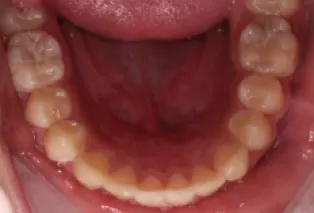

Photos intra-orales après traitement